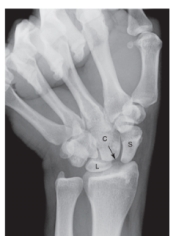

7

-Refer to the figure. Name the view.

A) Ulnar deviation

B) PA wrist

C) Radial deviation

D) Clenched fist

8

-Refer to the figure. The arrow indicates the capitate is moving into an interval between the scaphoid and the lunate. This sign is diagnostic for:

A) Dynamic instability

B) Tear of the triangular fibrocartilage complex

C) Avascular necrosis of the lunate

D) Fracture of the distal radius